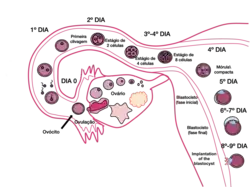

Desenvolvimento embrionário

Nos seres humanos, a embriogénese, ou período embrionário, tem início com a fecundação e prolonga-se até ao início do período fetal. Após a fecundação, o zigoto desloca-se lentamente ao longo da trompa de Falópio em direção ao útero. Ao longo desta viagem de mais de uma semana, o zigoto divide-se em células idênticas. Esta divisão celular tem início aproximadamente entre 24 a 36 horas após a fecundação. Ao fim do 4º dia de divisão celular, o zigoto dá origem a uma esfera sólida de 16 ou 32 células denominada mórula. Ao chegar ao útero, cinco dias após a fecundação, esta esfera apresenta-se oca e tem entre 50 e 100 células. Nesta fase passa a ser denominada blastócito, demorando cerca de seis dias até nidificar na parede uterina. O revestimento de proteínas do blastócito dissolve-se, o que permite às suas células trofoblásticas entrar em contacto e aderir às células endometriais da parede uterina. O embrião une-se com o endométrio através de um processo denominado nidação, que ocorre oito a dez dias após a ovulação. Após alguns dias, forma-se o celoma extra-embrionário que se tornará na cavidade coriónica, a qual irá conter o embrião, o líquido amniótico e o cordão umbilical. Desenvolve-se também a cavidade amniótica entre o citotrofoblasto e a massa de células interna. Desenvolve-se também a placa pré-cordal, que indica o futuro local da boca e da região cranial. Nesta fase, o embrião cresce rapidamente e começam a tomar forma as principais características externas. Este processo, denominado diferenciação celular, produz os diferentes tipos de células do organismo.[41][42][43]

Durante a quarta semana de idade gestacional (segunda semana de idade embrionária), as células trofoblásticas que envolvem as células embrionárias penetram profundamente no revestimento uterino, formando a placenta e as membranas embrionárias. Começa-se também a formar a vesícula vitelina, as células embrionárias formam um disco embrionário com duas células de espessura, desenvolve-se a linha primitiva e aparecem as vilosidades coriónicas. Na quinta semana de idade gestacional (terceira semana de idade embrionária) tem início a gastrulação, forma-se a corda dorsal no centro do disco embrionário, começa-se a formar o que virá a ser a medula espinal, com uma saliência que corresponderá ao cérebro, e aparecem os primeiros neurómeros. Já no final da semana, começam também a formar-se os vasos do coração primitivo e a desenvolver-se vascularização no disco embrionário.[44]